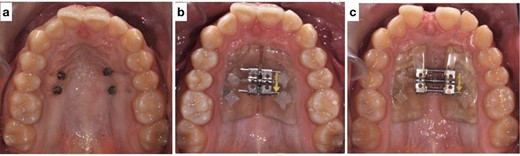

(a) Mini screws placed for the skeletally anchored rapid palatal expander. (b) Pre-expansion photo of the skeletally anchored rapid palatal expander; (c) post-expansion photo of the skeletally anchored rapid palatal expander.